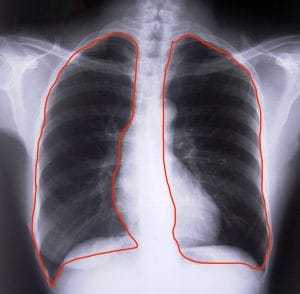

Only inhalation through the nose activates the diaphragm, a muscle used to completely fill the lungs. Without use the diaphragm atrophies, leaving you with less oxygen carrying capacity.

The lungs diffuse oxygen from inhaled air into the bloodstream. From there hemoglobin, the oxygen-carrying component of blood, transports oxygen to your tissues. Higher CO2 in your blood “unlocks the door” for hemoglobin to deliver more oxygen to tissues.